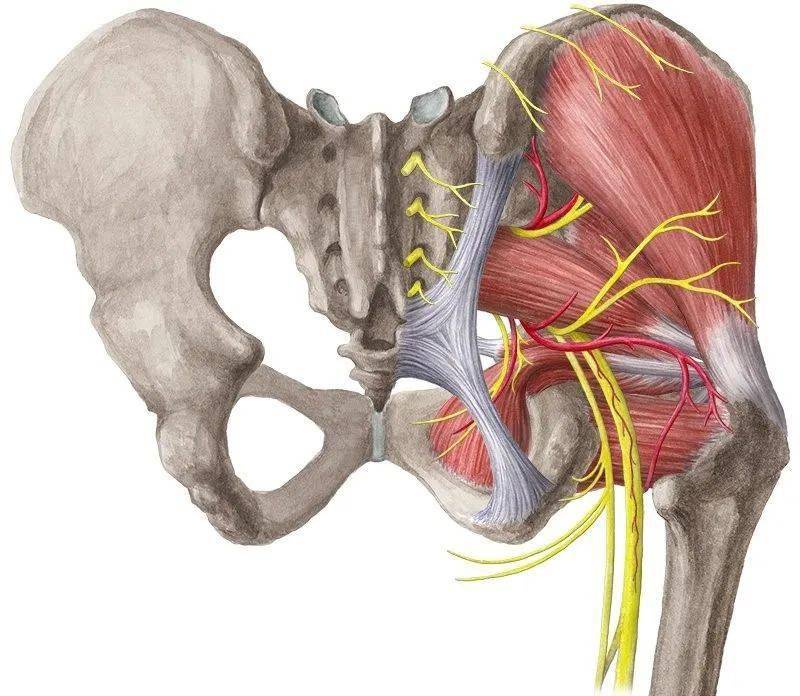

坐骨神经与梨状肌

坐骨神从梨状肌下缘通过出盆腔,因为梨状肌与坐骨神经的密切解剖关系